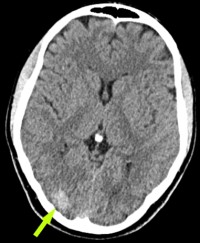

- Pre-Op